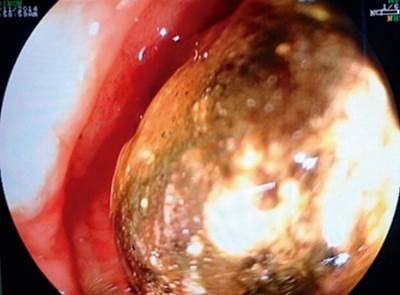

En TACab se evidencia obstrucción intestinal por imagen intraluminal a nivel de la primera porción duodenal de 4,5 x 3 cm (Figura 1 y 2) asociado con neumobilia y presencia de paso del medio de contraste a la vía biliar, lo que cumple los criterios de la triada de Rigler, adicionalmente dilatación de la cámara gástrica secundaria a obstrucción de la luz duodenal y una EVDA con presencia de cálculo impactado en el bulbo duodenal (Figura 3 y 4).

Con el advenimiento de las ayudas diagnósticas y la disponibilidad de las mismas se ha realizado un adecuado diagnóstico prequirúrgico, siendo la tomografía axial computarizada clave, la cual alcanza una sensibilidad y especificidad de 93% y 100%, respectivamente, para el diagnóstico. La endoscopia de vías digestivas altas es muy útil en el diagnóstico de esta patología y es considerada el método de referencia para su diagnóstico, como se demostró en el caso reportado, en donde se realizaron los dos exámenes. Las fístulas bilioentéricas pueden variar entre fístula colecistocólica, colecistogástrica o colecistoduodenal, siendo esta última la más frecuente, con 60% de los casos. Las principales características imagenológicas son presencia de neumobilia, cuerpo extraño alojado en la luz duodenal, obstrucción intestinal con dilatación duodenal y fístula bilioentérica, los cuales concuerdan con la triada de Rigler y se encontraban presentes en nuestra paciente 9,10.